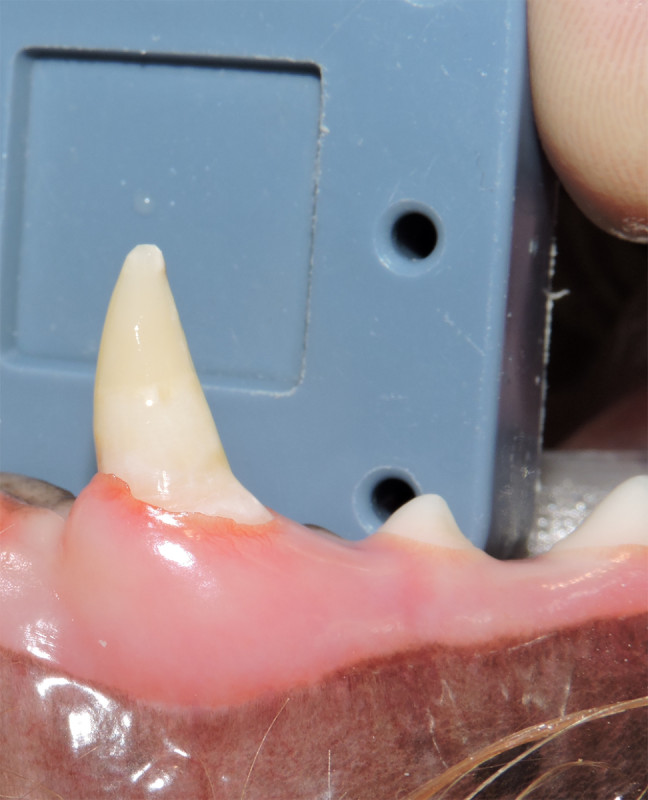

Vital Pulp Therapy

Young dogs less than 1 year of age that have very recently (less than 48 hours) fractured a tooth may be a candidate for vital pulp therapy. This procedure keeps the tooth alive and is very minimally invasive. For best results, this procedure should be performed within 48 hours of the tooth fracture. If your pet is not a candidate for this procedure, root canal therapy can still be performed to preserve the structure and function of the tooth. Vital pulp therapy can also be used to treat malocclusions.